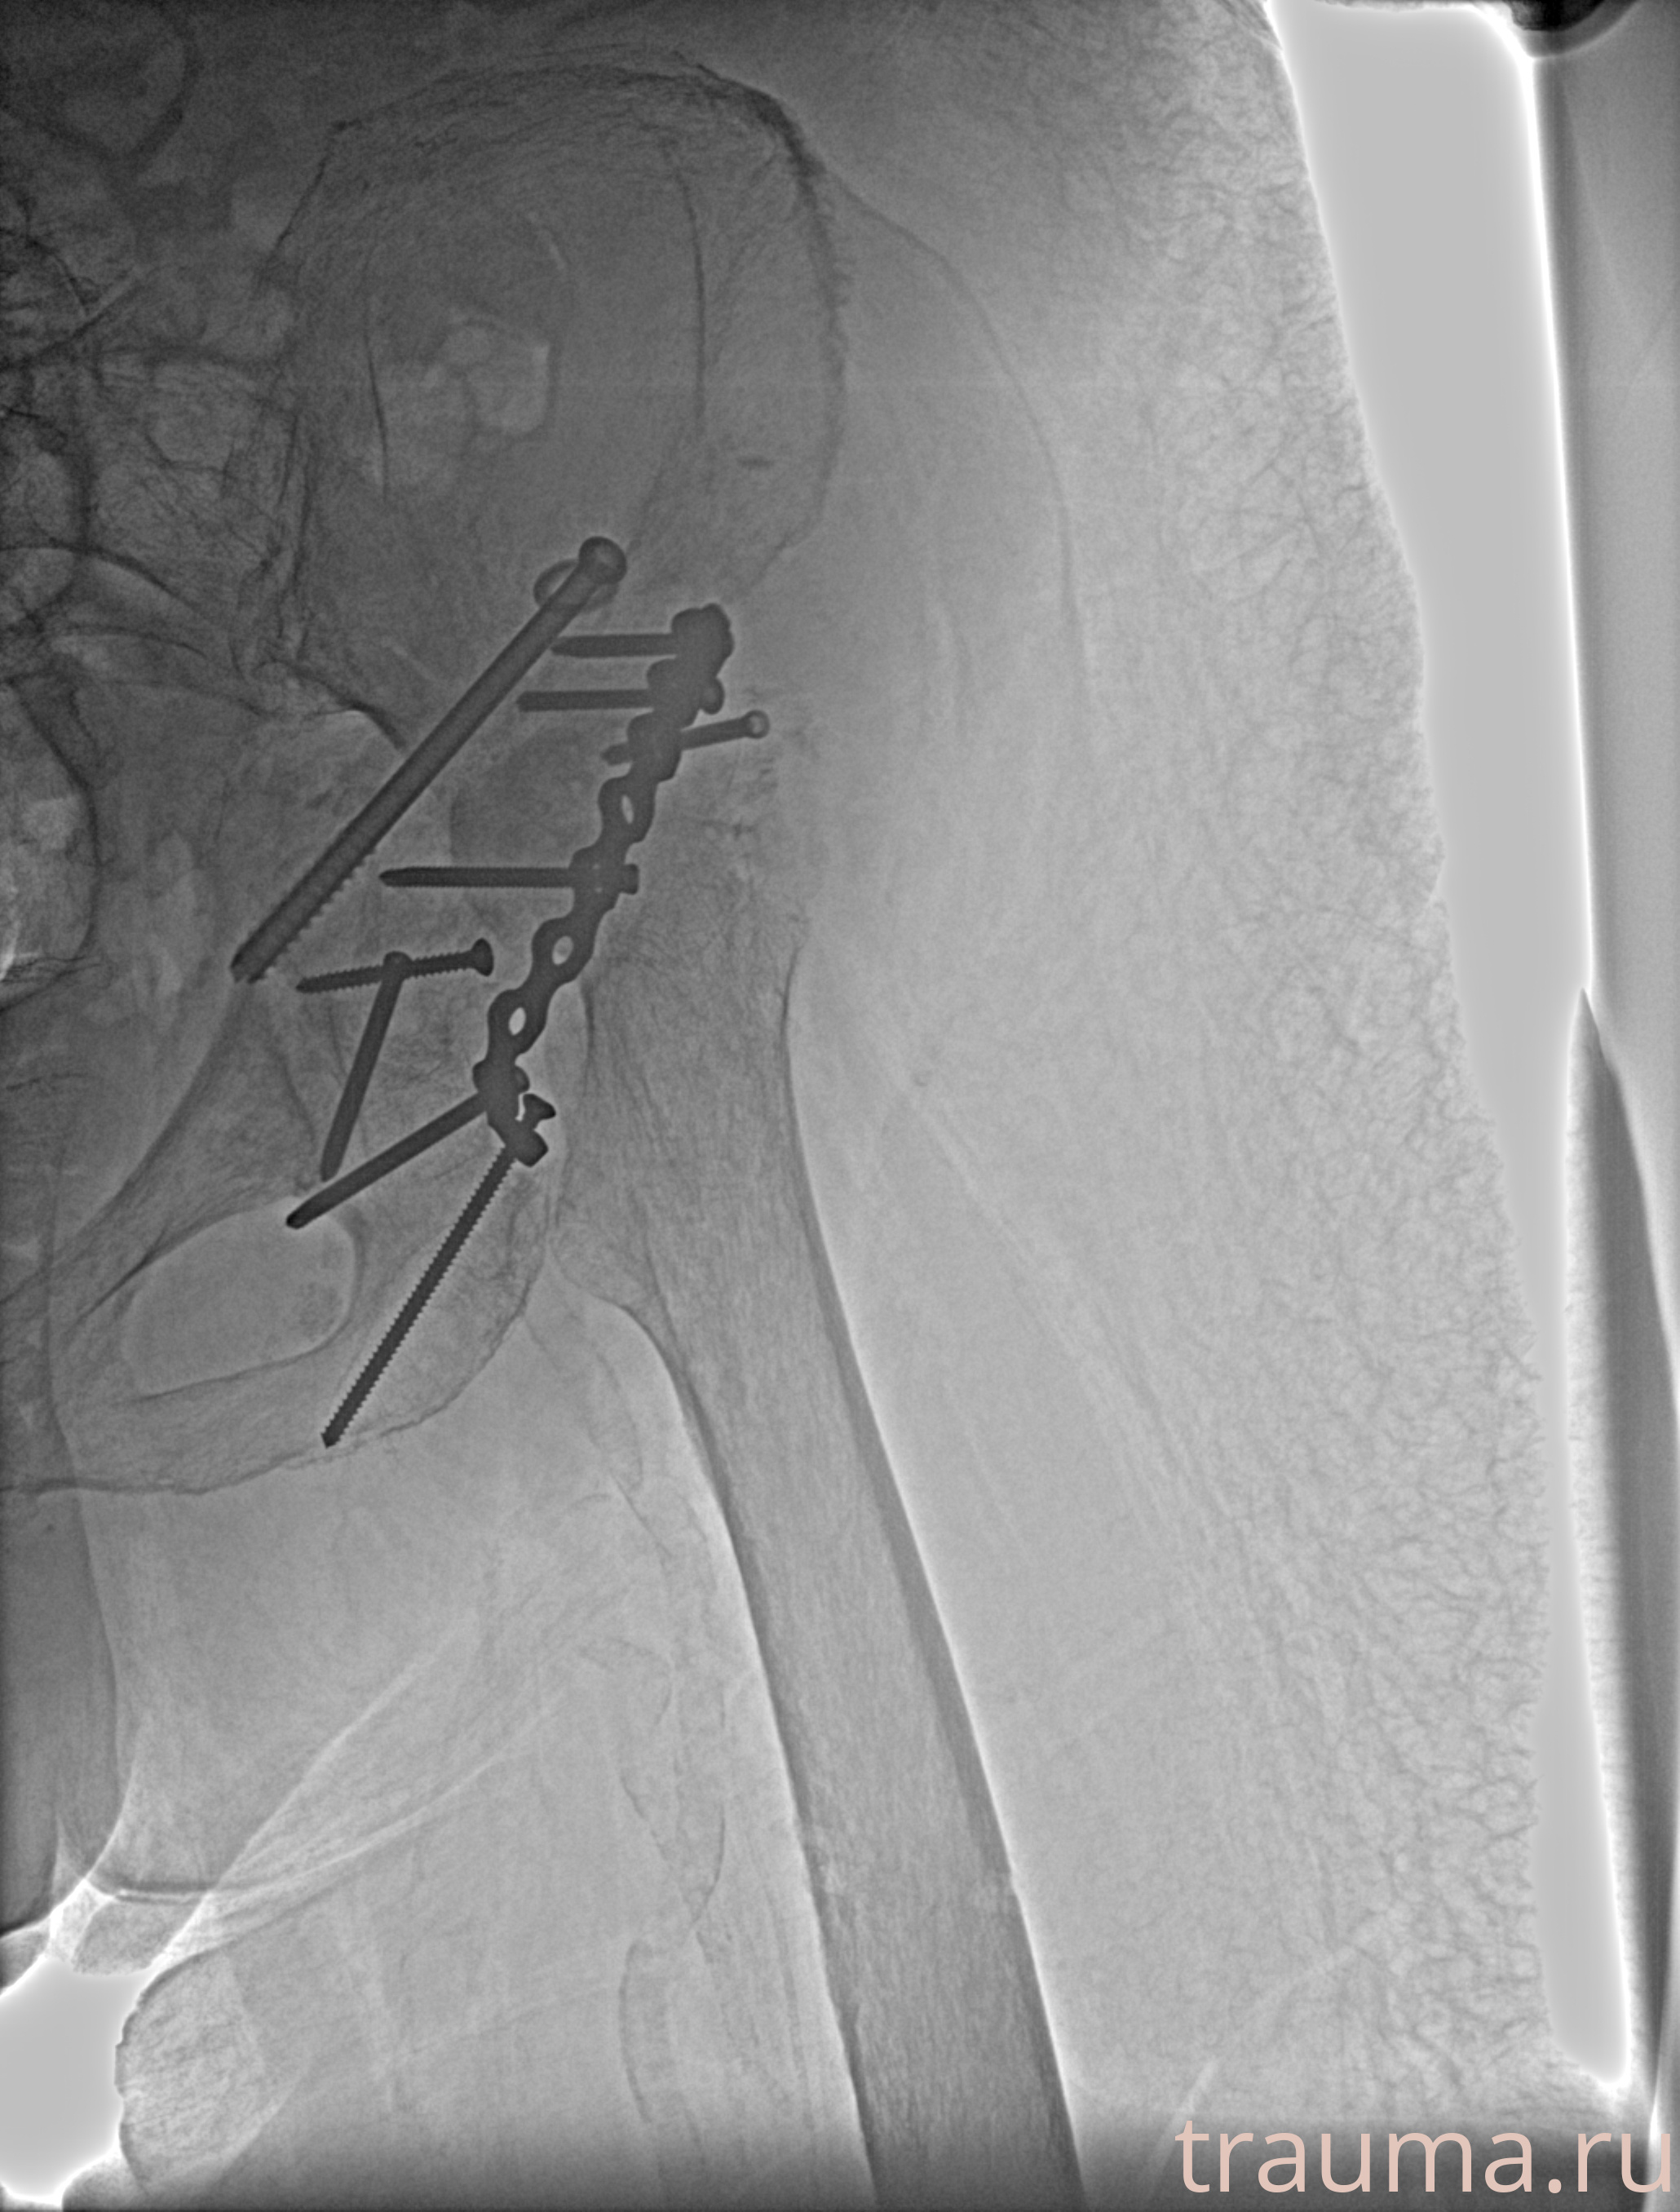

Рентгенограммы